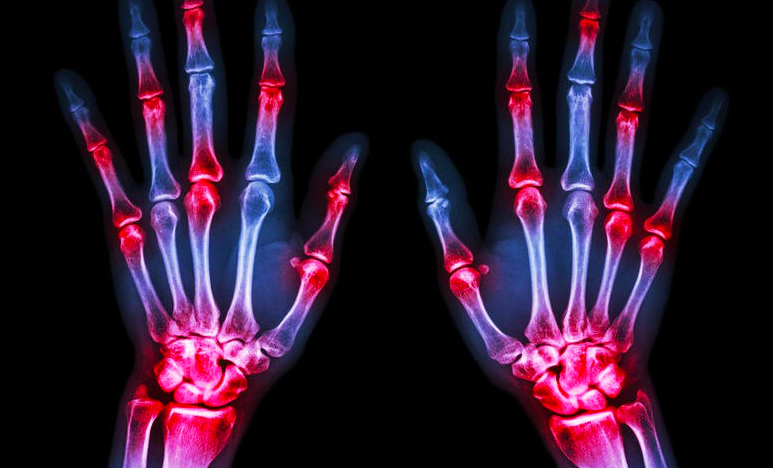

Now sometimes the sounds are more like are bones rubbing and grinding against each other. These are not mere harmless pops. This can be a sign of damaged cartilage, worn out cartilage or even inflammation. When cartilage gets worn out, it leaves a rough surface which could rub against our bones. Or it leaves the bones exposed to rub against one another. If this is the case, try to avoid high impact activity as to not aggravate it. Physiotherapy is recommended!